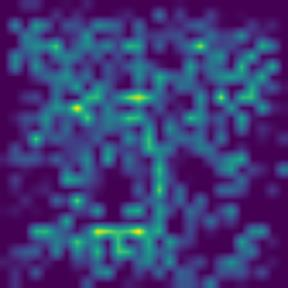

Microscopic image segmentation is a challenging task, wherein the objective is to assign semantic labels to each pixel in a given microscopic image. While convolutional neural networks (CNNs) form the foundation of many existing frameworks, they often struggle to explicitly capture long-range dependencies. Although transformers were initially devised to address this issue using self-attention, it has been proven that both local and global features are crucial for addressing diverse challenges in microscopic images, including variations in shape, size, appearance, and target region density. In this paper, we introduce SA2-Net, an attention-guided method that leverages multi-scale feature learning to effectively handle diverse structures within microscopic images. Specifically, we propose scale-aware attention (SA2) module designed to capture inherent variations in scales and shapes of microscopic regions, such as cells, for accurate segmentation. This module incorporates local attention at each level of multi-stage features, as well as global attention across multiple resolutions. Furthermore, we address the issue of blurred region boundaries (e.g., cell boundaries) by introducing a novel upsampling strategy called the Adaptive Up-Attention (AuA) module. This module enhances the discriminative ability for improved localization of microscopic regions using an explicit attention mechanism. Extensive experiments on five challenging datasets demonstrate the benefits of our SA2-Net model. Our source code is publicly available at \url{https://github.com/mustansarfiaz/SA2-Net}.